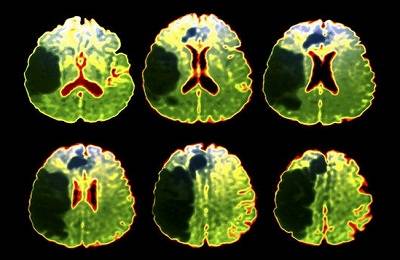

На первых порах для установки диагноза пациенту будет сделана магнитно-резонансная и / или компьютерная томография головы (в зависимости от предварительного диагноза, а также наличия соответствующего оборудования в клинике). Исследования понадобятся для того, что определить масштаб и локализацию поражения.

Пациент должен сразу же быть повергнуть обследованиям – МРТ и КТ головного мозга, чтобы определить, чем вызван и насколько распространен инфаркт. ЭКГ делается для анализа работы сердечно-сосудистой системы. Далее, общий анализ крови и выявление воспалительных процессов, уровня сахара в крови и т.п. Все это сочетается с программами нелекарственной реабилитации, описанными ниже.